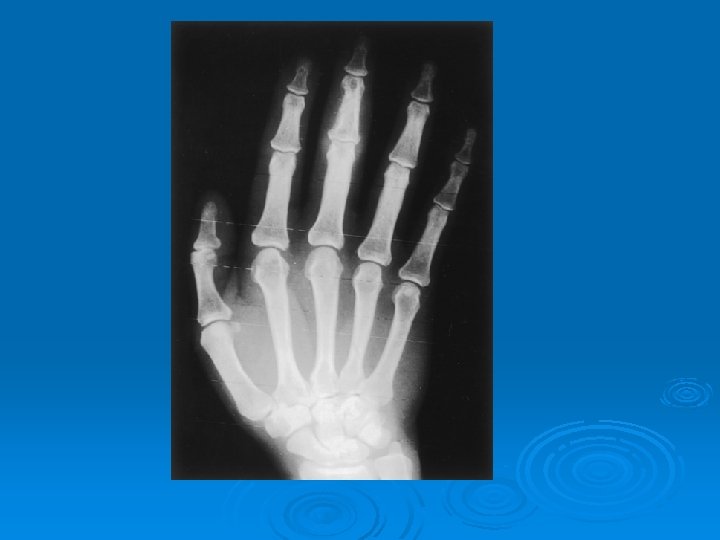

ELDE LİTİK LEZYONLAR